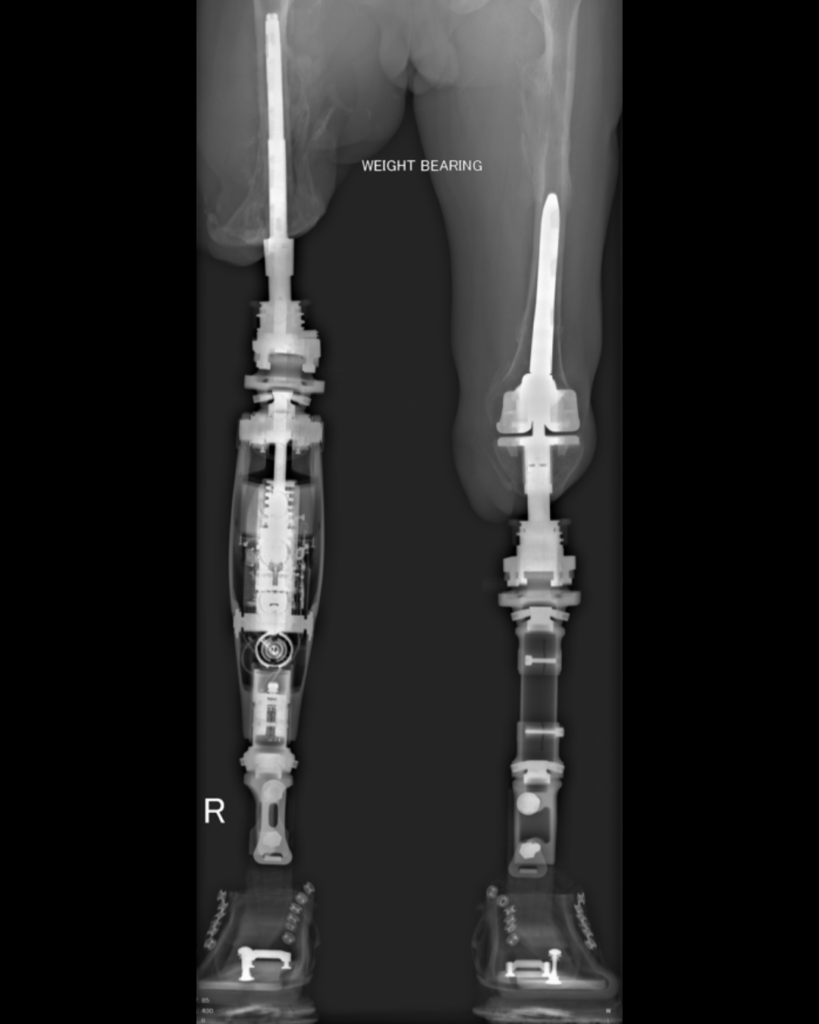

New study examines efficacy of Osseointegration in patients with Vascular Disease.

Peripheral vascular disease, or PVD, has traditionally been considered problematic for osseointegration due to concerns around impaired wound healing and the increased risk of post-operative